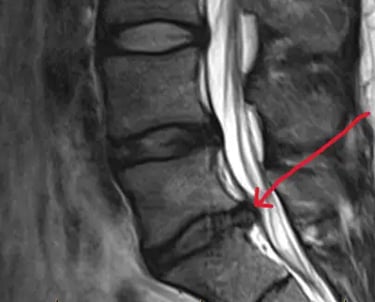

الانزلاق الغضروفي:

إعادة محاذاة الأقراص المنزاحة لتقليل الألم وتهيج الأعصاب.

يعمل علاج تخفيف ضغط الأقراص الفقرية على تطبيق شدٍّ لطيف ومُتحكَّم فيه على العمود الفقري، مما قد يساعد على تقليل الضغط داخل الأقراص الفقرية وتخفيف الضغط عن الهياكل المحيطة مثل الأعصاب والأنسجة الرخوة.